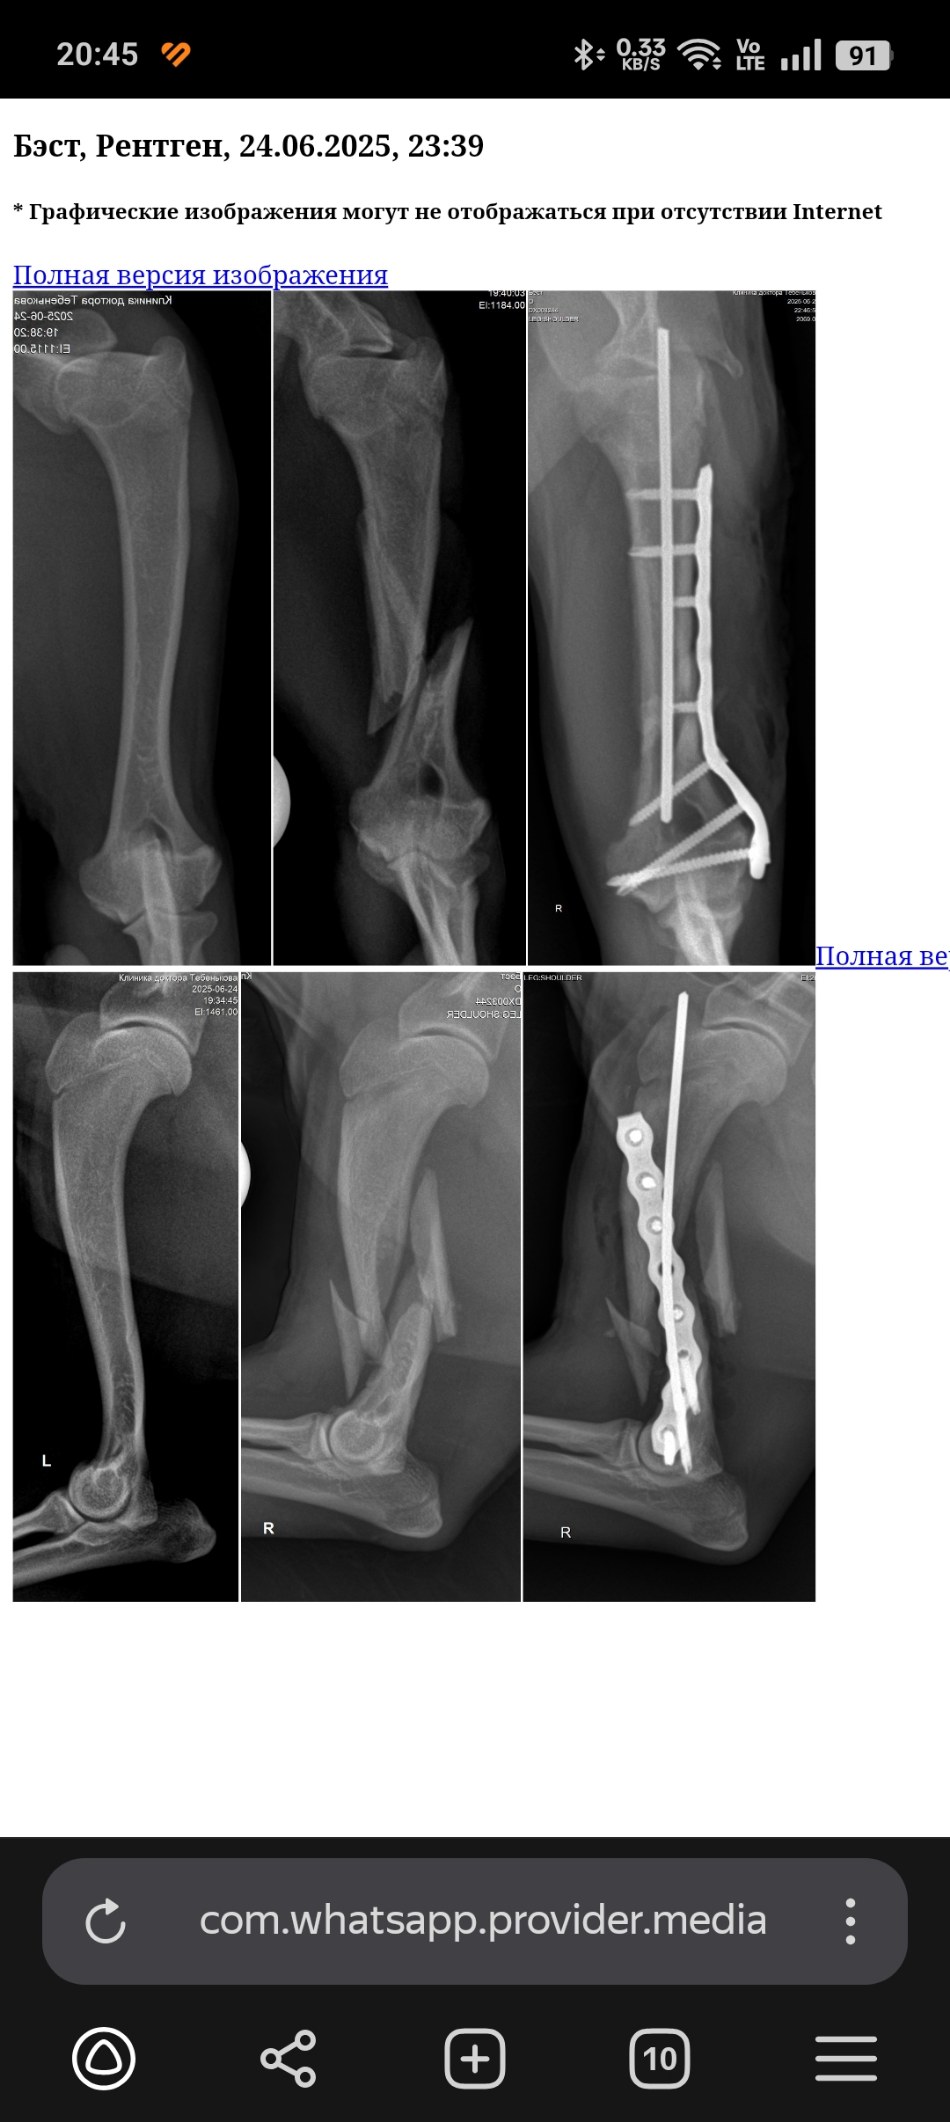

Рентген до и после

Найден с переломом плеча.